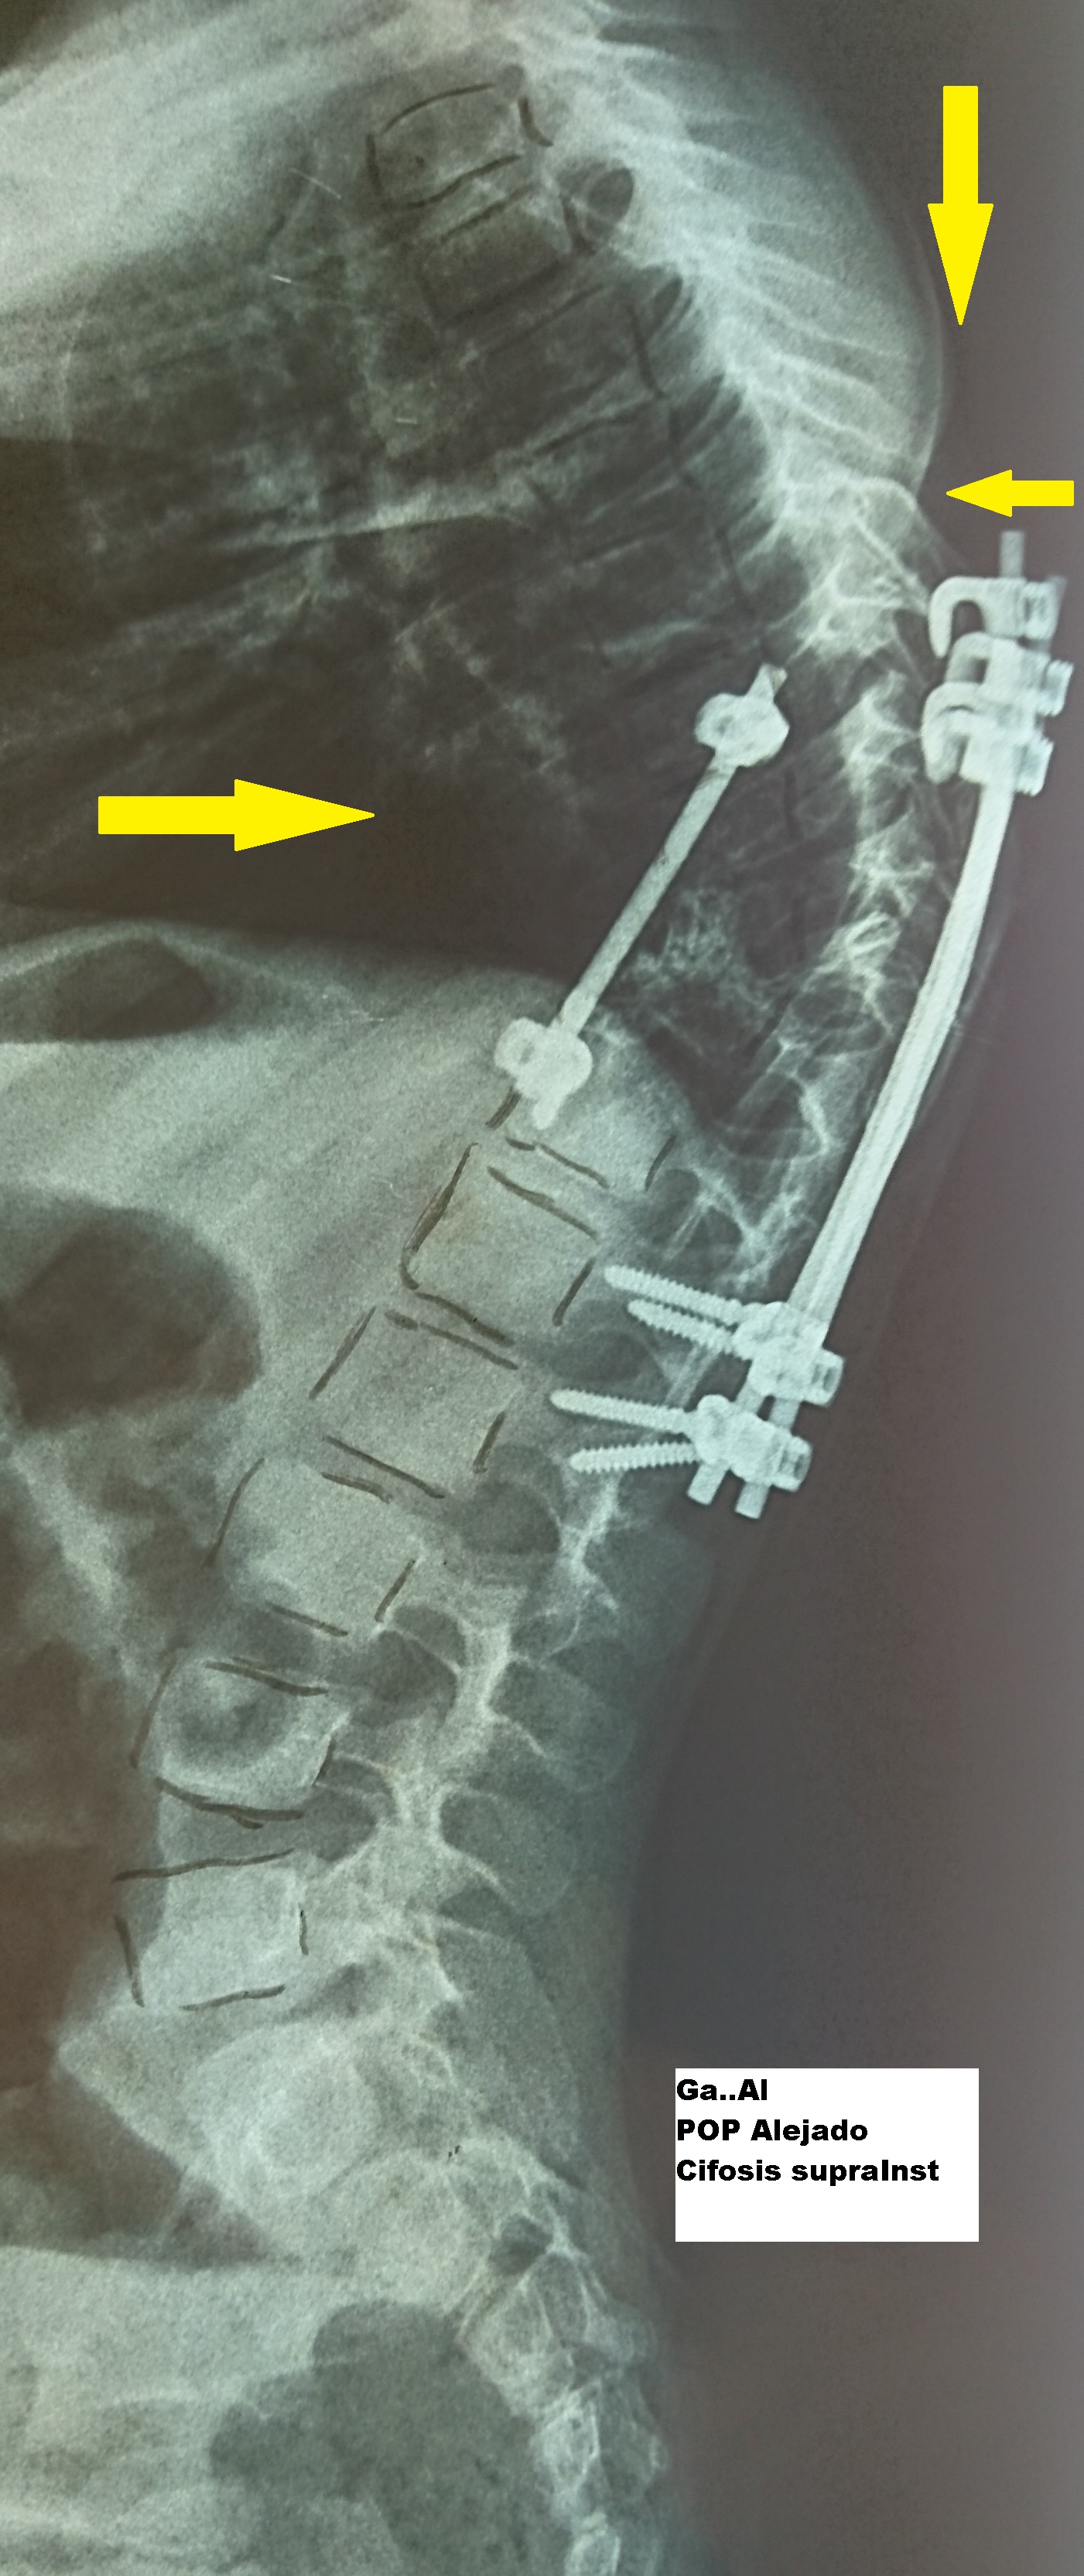

- Figura No 4a

- Figura No 4b

- Figura No 4c

- Figura 4 Texto